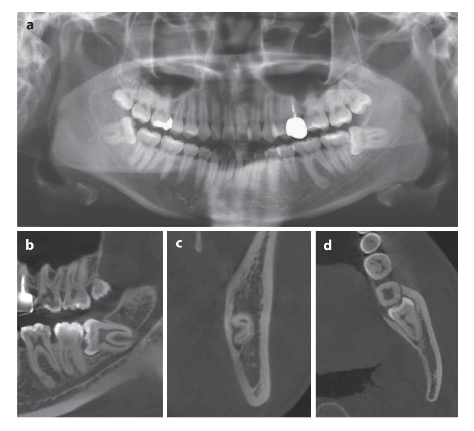

Las radiografías panorámicas suelen ser el primer paso para evaluar la posición de los terceros molares y su relación con estructuras cercanas. Sin embargo, en casos más complejos, la tomografía computarizada de haz cónico (CBCT) ofrece una visión tridimensional que resulta fundamental para una planificación más precisa.

Gracias a estas herramientas, es posible identificar la cercanía a estructuras sensibles como el nervio alveolar inferior o el seno maxilar, lo que reduce significativamente el riesgo de complicaciones.

Cada paciente es único, y la anatomía de los terceros molares puede variar considerablemente. Las raíces pueden ser múltiples, curvas o estar en estrecha relación con nervios importantes.

En el maxilar superior, por ejemplo, la proximidad al seno maxilar representa un desafío importante, mientras que en la mandíbula, la cercanía al nervio alveolar inferior exige extrema precaución.